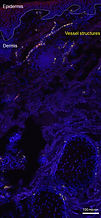

Vessel structures